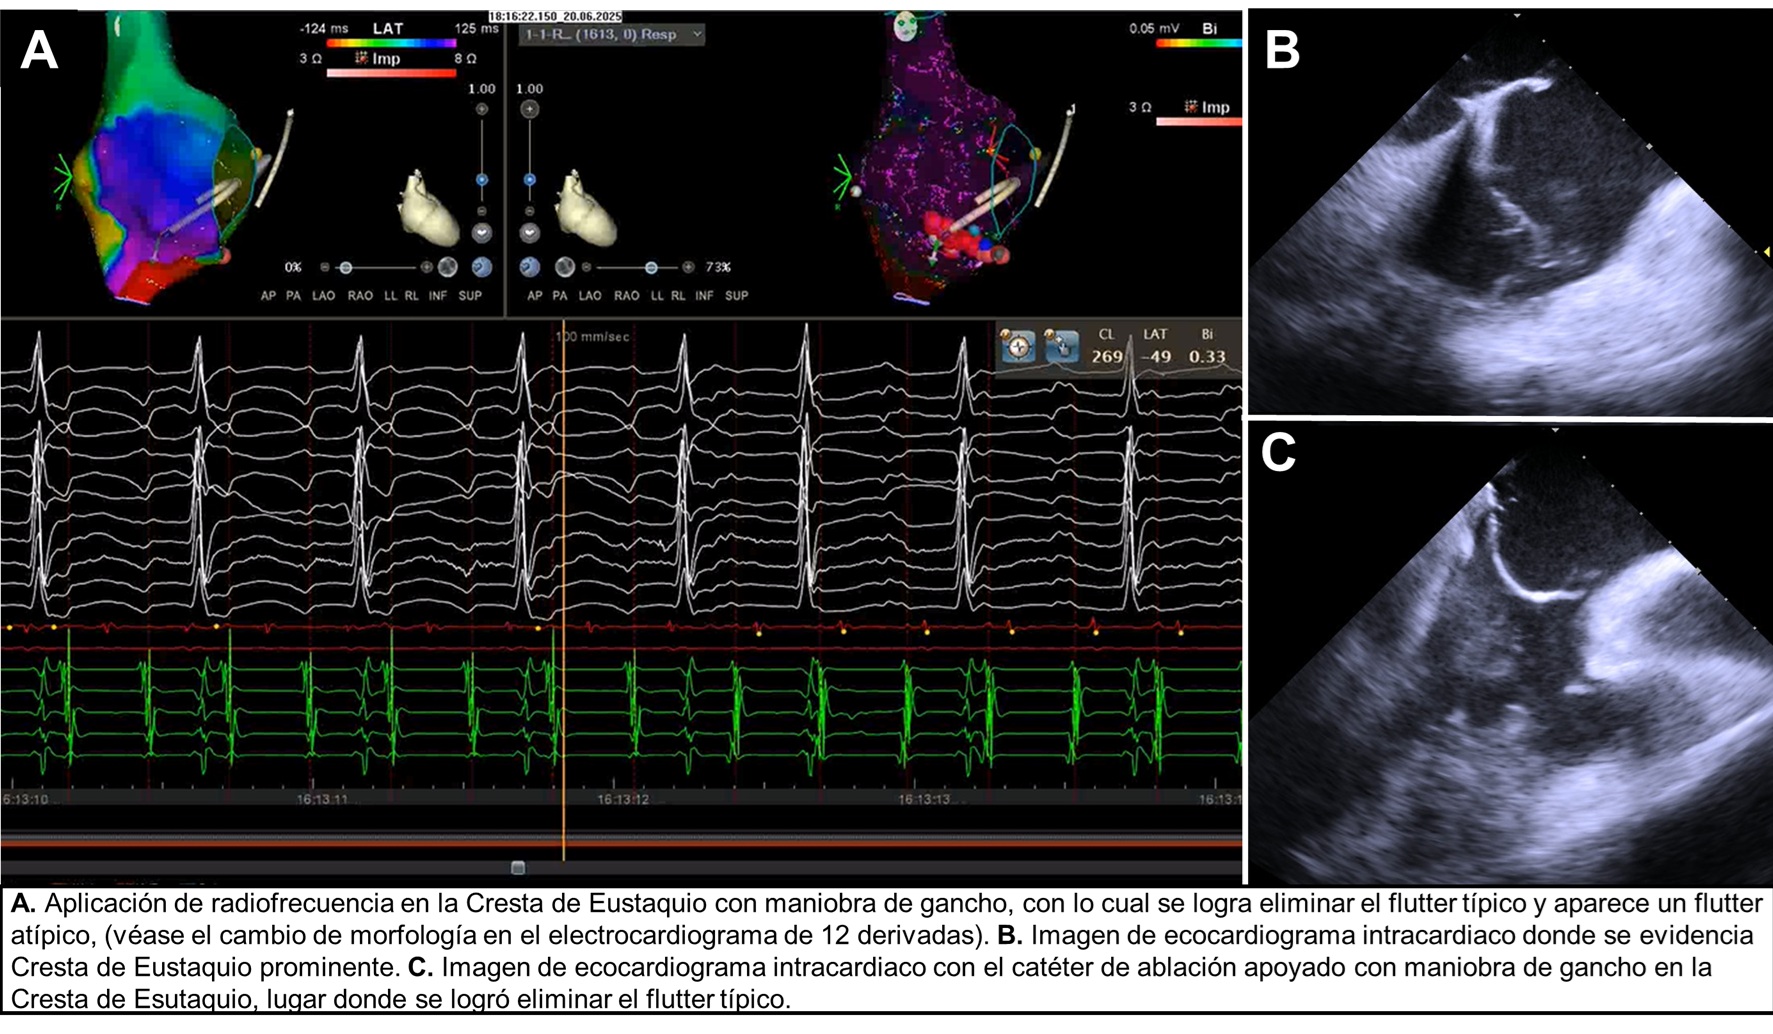

Background: Atrial flutter (AFL) is a common supraventricular arrhythmia, frequ...

Introducción:El aleteo auricular tipo I o típico es una taquiarritmia macroree...